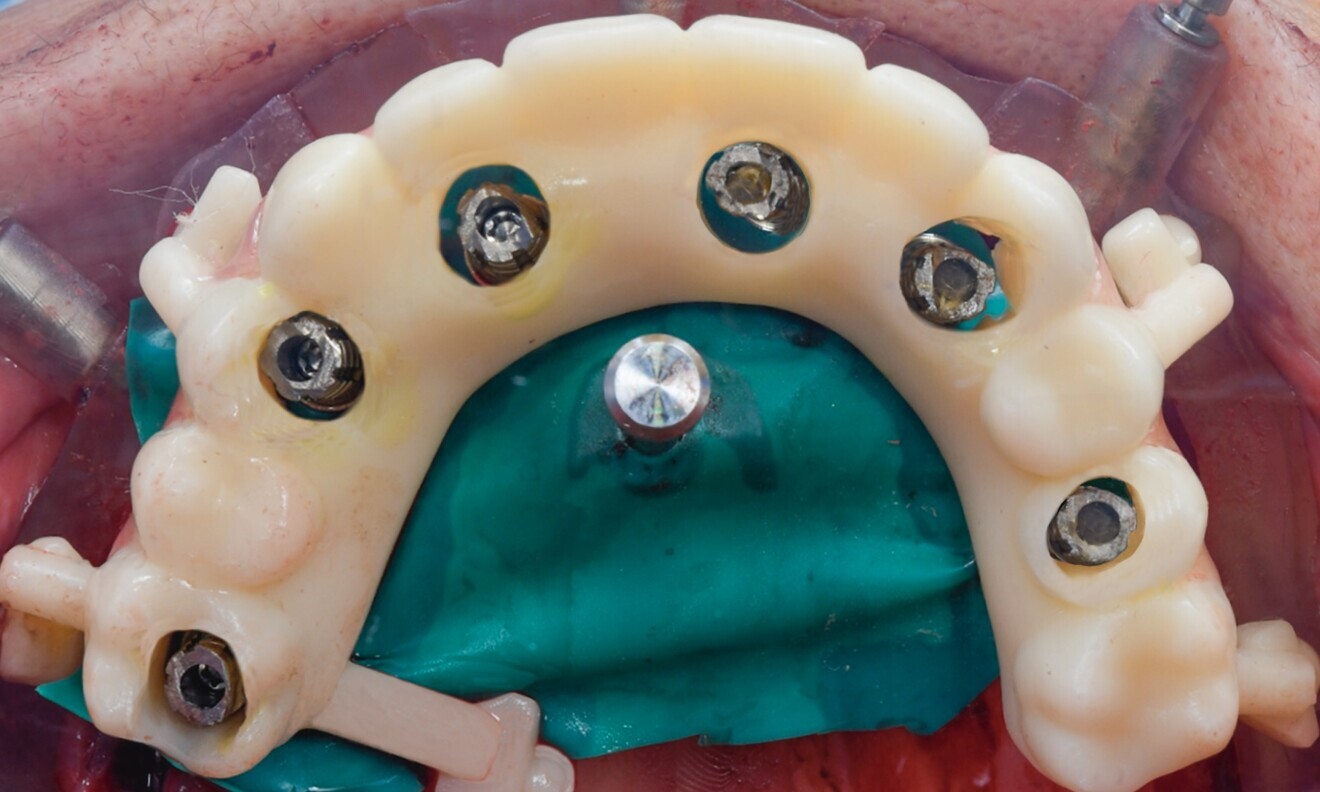

Six Straumann BLT implants made from the material Roxolid and with the SLActive surface (implant #16: 4.8 × 10.0 mm; implant #14: 4.1 × 14.0 mm; implant #12: 3.3 × 14.0 mm; implant #21: 4.1 × 12.0 mm; implant #23: 3.3 × 12.0 mm; implant #26: 4.1 × 14.0 mm) were placed (Fig. 8). The gaps were filled with Straumann XenoGraft, and six temporary titanium copings for screw-retained abutments were subsequently placed (Fig. 9).

Maxillary full-arch impressions were taken, employing appropriate impression copings for an open-tray approach using a polyether impression material (Impregum, 3M ESPE). After a few hours, a dental dam was placed around the temporary copings to protect the fresh surgical sites. The previously prepared temporary prosthesis produced from a resin-based provisional material was then affixed in place (Figs. 10–12).